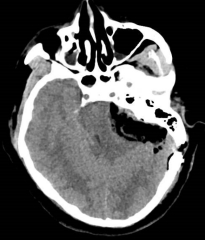

听神经瘤术前核磁 术后CT